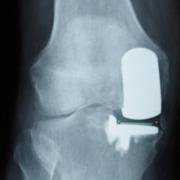

Tibiofemoral partial knee replacement, replacing one compartment of the joint.

Model bones to show the components of a total knee replacement. In fact this only shows replacement of the tibiofemoral joints, but the patellofemoral are generally also replaced.